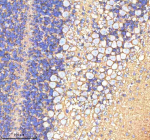

Immunohistochemical staining of ATP1A2 using anti-ATP1A2 antibody. ATP1A2 was detected in a paraffin-embedded section of mouse cerebellum tissue. Heat mediated antigen retrieval was performed in EDTA buffer (pH 8.0, epitope retrieval solution). The tissue section was blocked with 10% goat serum. The tissue section was then incubated with 2 ug/ml rabbit anti-ATP1A2 antibody overnight at 4oC. Peroxidase Conjugated Goat Anti-rabbit IgG was used as secondary antibody and incubated for 30 minutes at 37oC. The tissue section was developed using an HRP secondary and DAB substrate.

Immunohistochemical staining of ATP1A2 using anti-ATP1A2 antibody. ATP1A2 was detected in a paraffin-embedded section of rat cerebellum tissue. Heat mediated antigen retrieval was performed in EDTA buffer (pH 8.0, epitope retrieval solution). The tissue section was blocked with 10% goat serum. The tissue section was then incubated with 2 ug/ml rabbit anti-ATP1A2 antibody overnight at 4oC. Peroxidase Conjugated Goat Anti-rabbit IgG was used as secondary antibody and incubated for 30 minutes at 37oC. The tissue section was developed using an HRP secondary and DAB substrate.